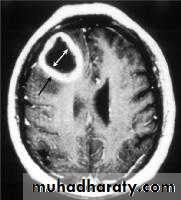

ACUTE INFARCTION

* wedge shape hypo density area.* Shifting of the midline & frontal horn